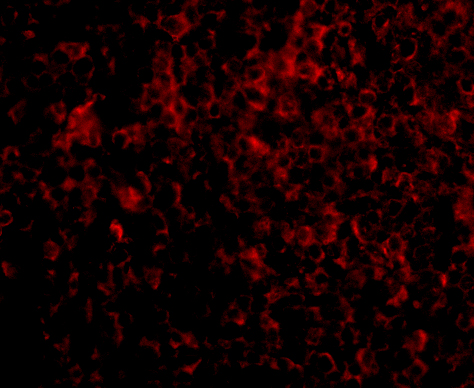

ATG5 antibody can be used for the detection of ATG5 by Western blot at 1 - 2 μg/mL. Antibody can also be used for immunohistochemistry starting at 2.5 μg/mL. For immunofluorescence start at 5 μg/mL.

Antibody validated: Western Blot in rat samples; Immunohistochemistry in human samples and Immunofluorescence in human samples. All other applications and species not yet tested.